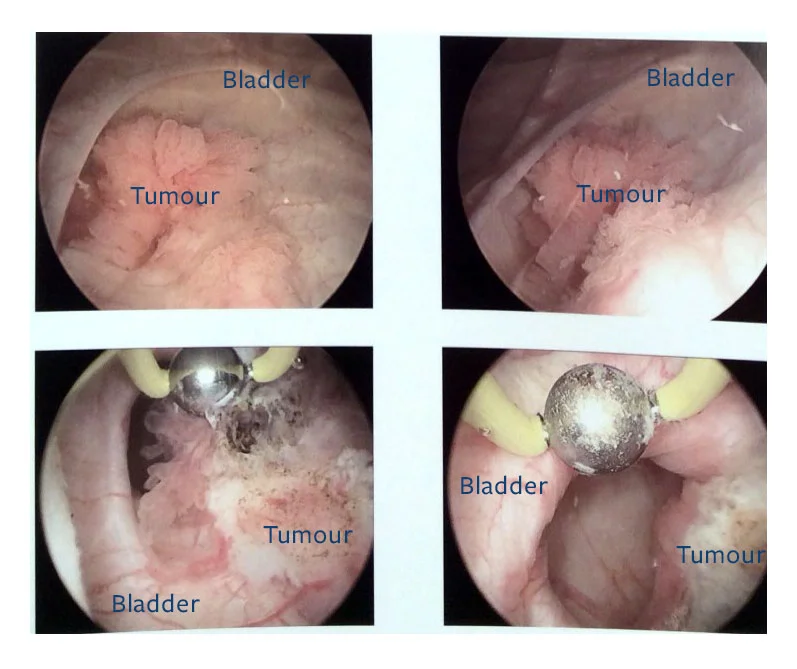

Cystoscopic image of polypoid urinary bladder tumor. Image courtesy of …

Cystoscopic findings in bladder tumors. (a) White light mode (left …

Enhanced Cystoscopy for Early Bladder Cancer – PeopleBeatingCancer

Blue Light Cystoscopy Increases Bladder Cancer Detection Rate – Renal …

Imaging modalities for improved bladder tumor detection. Papillary and …

Imaging modalities for improved bladder tumor detection. Papillary and …

Tumors of the Bladder: Cystoscopic and Radiographic Appearance